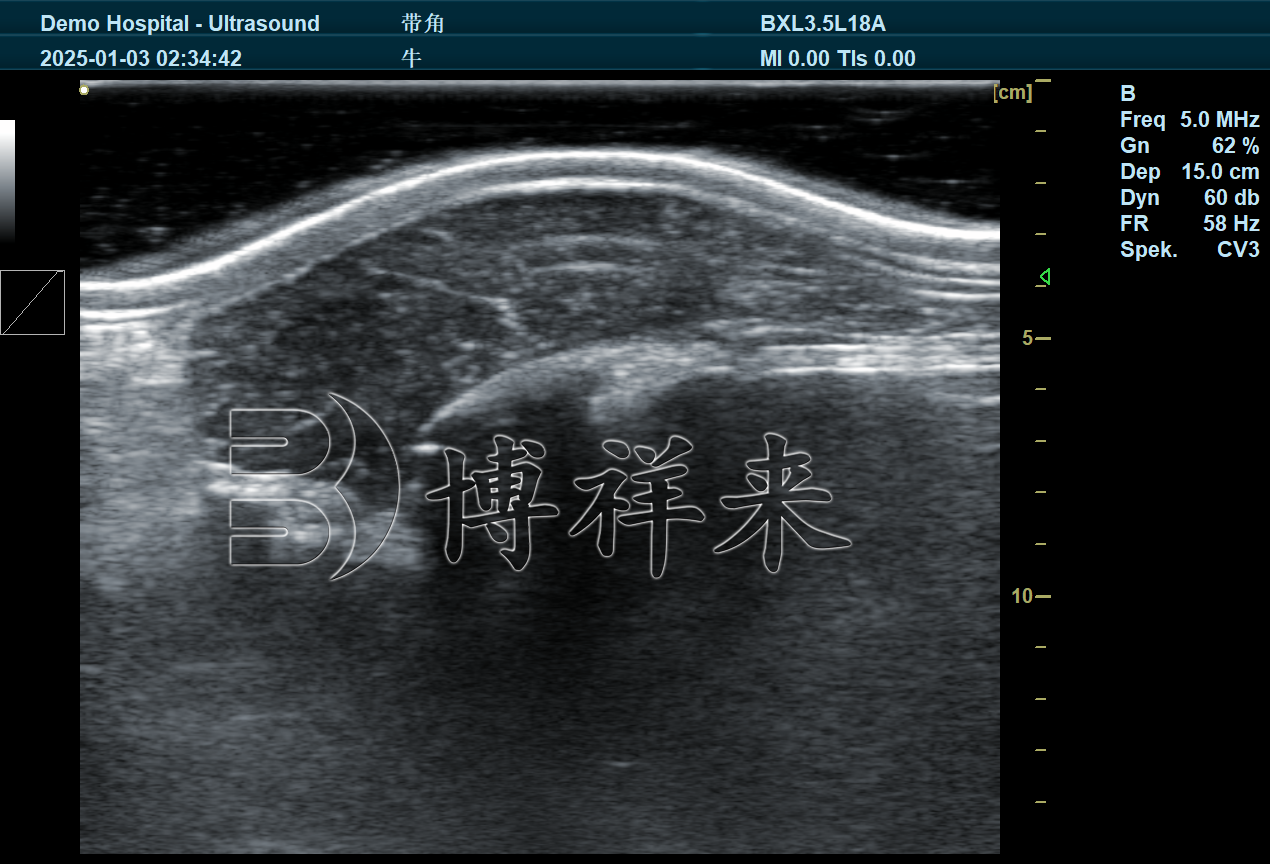

传统的肉牛体况评估往往依赖人工触诊、目测或屠宰后指标,无法在育肥阶段实时获取肌内脂肪水平。通过B超测背膘和眼肌等部位影像分析,不仅可以测量肉牛背膘厚度和眼肌面积,还可以进一步根据超声图像特征估算肌内脂肪含量。这种基于图像的检测方式,使育肥阶段的肉质评价更科学、更可量化,有助于生产管理者调整饲喂策略,实现更稳定的终端肉质表现。